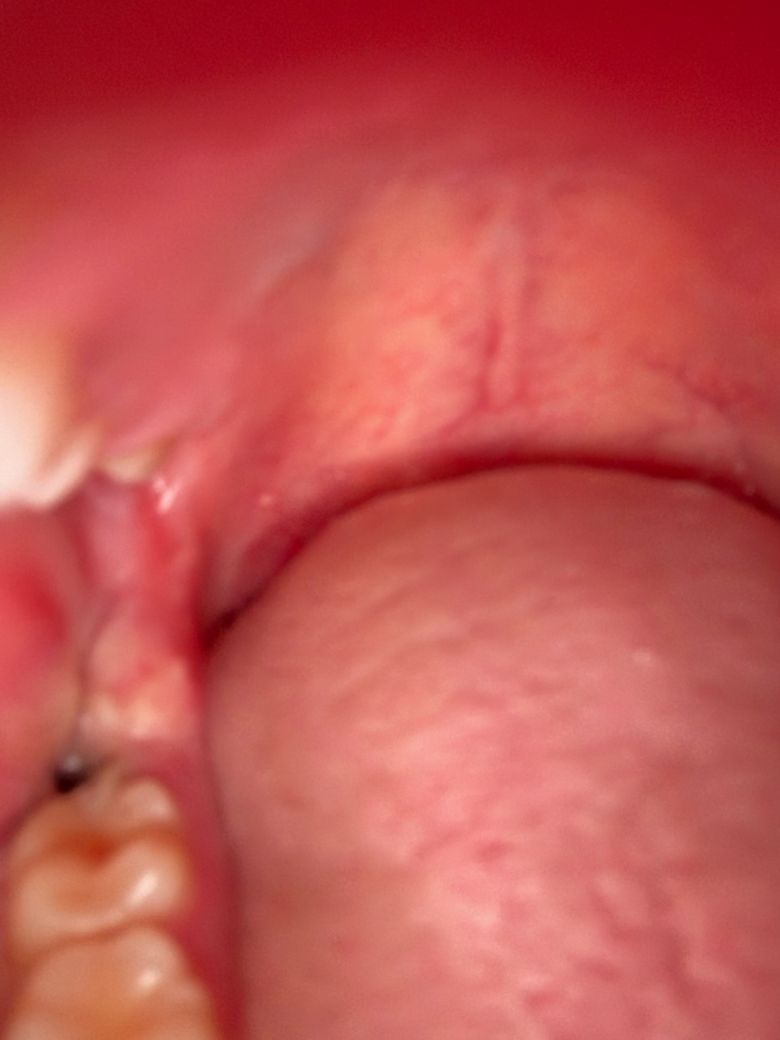

수요일날 발치를 했는데요 원래 피떡이 있던 자리에 지금보니 저렇게 크기도 훨씬작아지고 색깔이 거의 검정색에서 회색으로 보이게 변했어요 특히 크기가 엄청작아지고 주변에 하얀색으로 덮혔습니다 드라이소켓이 구취나고 회색으로 변한다던데 혹시 드라이소켓일 가능성이 있나요??ㅠㅠ

• 1번 째 사진

드라이소켓은 통증이 극심하기 때문에 아닐 것이며 사진상으로도 특별히 문제는 보이지 않습니다.

지금으로선 특별히 치유에 문제가 있어 보이진 않습니다 발치 후 주의사항 잘 지키시면 됩니다